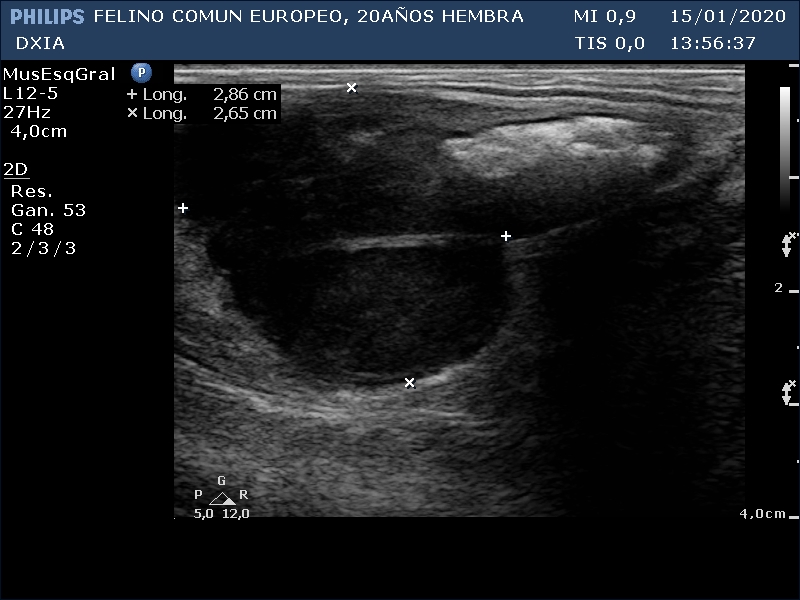

FRANGELICA

Se realiza ecografía y se observa alteración compatible con neoformación en asa del intestino delgado.

Asa del ID con aumento de grosor de su pared, pérdida de estructura en capas. Neoformación hipoecogénica.

Ganglio yeyunal con aspecto globoso, hipoecogénico y bastante homogéneo, índice mayor de 0.5. Compatible con mayor probabilidad con proceso tumoral o metastásico.

Asa del ID con neoformación sin definición de capas intestinales.